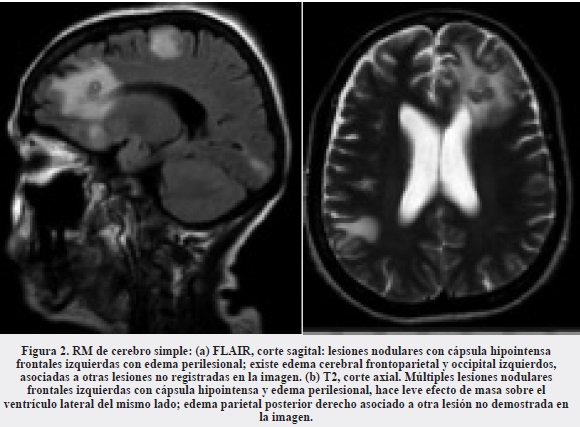

Se trata de una mujer de 48 años de edad, ama de casa, procedente del área rural de Arauquita (Arauca), VIH negativa, sin antecedentes patológicos de importancia, que consultó inicialmente al Hospital Erasmo Meoz de Cúcuta por tos, expectoración de color marrón y pérdida de peso con dos semanas de evolución. Entre el 13 de marzo y el 23 de diciembre de 2011 estuvo hospitalizada en cuatro oportunidades, en la primera por un proceso infeccioso neumónico, en la segunda por persistencia de la infección pulmonar, presencia de abscesos de tejidos blandos y artritis séptica de cadera derecha; en esta hospitalización se diagnosticó la nocardiosis diseminada debido al aislamiento de Nocardia spp. del cultivo de masa pulmonar. En la tercera hospitalización se encontró afectación encefálica además de pulmonar y requirió una cuarta hospitalización por persistencia de la infección del sistema nervioso central y por la diseminación al ojo izquierdo. En la Tabla 1 se detallan las principales manifestaciones clínicas, los hallazgos de los exámenes paraclínicos y la terapia utilizada. Las imágenes diagnósticas de las lesiones pulmonares y encefálicas se presentan en las Figuras 1, 2 y 3. La paciente finalmente mejoró de su cuadro clínico y quedó como secuela la pérdida de la visión por el ojo izquierdo.

La infección pulmonar por Nocardia es poco frecuente pero grave, especialmente en el paciente inmunosuprimido. Se puede confundir con otras enfermedades supurativas del pulmón y con enfermedades malignas. La enfermedad pulmonar es la forma de presentación clínica más común de la nocardiosis y representa el 40% de los casos. De estos, aproximadamente en 90% es causada por miembros del complejo Nocardia asteroides. Se presenta como una neumonía aguda, frecuentemente necrotizante y asociada con cavitación, como observamos en nuestra paciente (9). Otras presentaciones clínicas incluyen nódulos pulmonares indolentes de agrandamiento progresivo o neumonía asociada con empiema. Los pacientes pueden presentar fiebre, escalofríos, tos productiva, suduración profusa, pérdida de peso, anorexia, disnea y hemoptisis. Estos síntomas son también frecuentes en las infecciones por micobacterias y por Actynomices. El patrón radiológico incluye nódulos, infiltrados neumónicos reticulonodulares o difusos, abscesos simples o múltiples y áreas de consolidación con o sin cavitación (Figura 1). Frecuentemente, hay diseminación hematógena especialmente al SNC (33% de los casos), como la presentada en nuestra paciente (Figuras 2 y 3). Por ello, todo paciente con nocardiosis debería tener imágenes del SNC para investigar siembras en ese lugar. En estos casos, los pacientes presentan signos de sepsis, hipertensión intracraneana o hallazcos focales neurológicos, como en nuestro caso, que consultó por convulsiones (9). En Colombia se han informado casos de nocardiosis del SNC en sus diferentes formas de presentación clínica (11-14).

Los hallazgos de las imágenes cerebrales dependen del estado del proceso infeccioso, el cual puede variar desde la cerebritis hasta la franca formación de absceso. En el estado de absceso, los restos necróticos se acumulan en el centro, mientras se forma a su alrededor una cápsula de colágeno. Estos restos necróticos contienen material proteináceo, el cual tiene una señal de intensidad más alta que la del LCR en las imágenes ponderadas en T1 y en las de inversión-recuperación de la resonanacia magnética, rodeadas de un edema cerebral de grado moderado. En las imágenes de T1 la cápsula del absceso resalta sobre el centro necrótico y el edema perilesional como un anillo isointenso o ligeramente hiperintenso. En las imágenes del T2 este anillo es consistentemente hipointenso. La cápsula es hiperintensa ya sea debido a hemorragia cerebral, a la metahemoglobina paramagnética que causa aumento de la señal en las imágenes en T1, o por la presencia de abundantes radicales libres dentro de los macrófagos de la cápsula del absceso. La actividad de los macrófagos es más alta en la cerebritis tardía y en la fase inicial del absceso, tiempo durante el cual la cápsula se muestra marcadamente hipointensa en las imágenes de T2 (Figura 2) (15). En las imágenes de T2 se pueden ver múltiples anillos concéntricos en los abscesos, hallazgo que pudiera ser específico de la nocardiosis encefálica. Estos anillos pueden ser debidos a la organización de las bridas necróticas y a la fagocitosis por parte de los macrófagos en la cápsula (16). Los abscesos presentan realce anular con el medio de contraste, el cual puede persistir hasta por ocho meses después del tratamiento y que no se debe interpretar como falla terapéutica, como observamos en nuestro caso (Figura 3). Son signos confiables de buena respuesta la disminución de tamaño del centro necrótico y de la hipointensidad capsular en las imágenes de T2 (15).